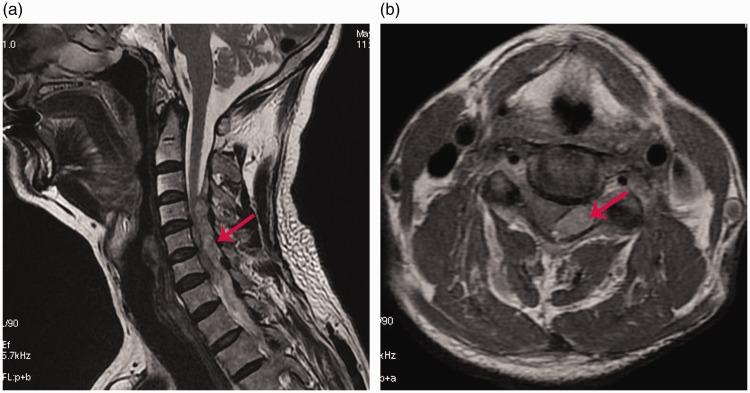

This report describes a case of idiopathic cervical spinal subdural haematoma (SSDH) in which the haematoma was spontaneously absorbed without any treatment. A 68-year-old male patient presented with persistent neck pain and no obvious cause. Magnetic resonance imaging (MRI) revealed a space-occupying lesion at the C4-T1 levels. The lesion was initially misdiagnosed as a tumour. An operation was arranged to remove the tumour, but a preoperative computed tomography scan showed no obvious abnormal soft tissue density in the cervical spinal canal. Repeat enhanced MRI showed degeneration of the cervical vertebrae, but no obvious abnormal soft tissue density and no obvious enhanced signals in the cervical spinal canal. Spontaneous resolution of an idiopathic cervical SSDH was considered. Idiopathic cervical SSDH without obvious neurological symptoms are difficult to diagnose, so suspected cases should be carefully monitored. If the neurological symptoms grow progressively more debilitating with time, emergency surgery might need to be considered. To avoid unnecessary surgery, conservative management should be an option for patients with minimal neurological deficits and re-examination with MRI could be the best way to observe the dynamic changes taking place in the idiopathic cervical SSDH.

本报告描述了一例特发性颈段脊髓硬膜下血肿(SSDH),该血肿未经任何治疗便自行吸收。一名68岁男性患者出现持续性颈部疼痛且无明显病因。磁共振成像(MRI)显示C4 - T1水平有占位性病变。该病变最初被误诊为肿瘤。安排了手术以切除肿瘤,但术前计算机断层扫描显示颈椎管内无明显异常软组织密度。重复增强MRI显示颈椎退变,但颈椎管内无明显异常软组织密度且无明显强化信号。考虑特发性颈段SSDH自行消退。无明显神经症状的特发性颈段SSDH难以诊断,因此对疑似病例应仔细监测。如果神经症状随时间逐渐加重,可能需要考虑紧急手术。为避免不必要的手术,对于神经功能缺损最小的患者,保守治疗应是一种选择,而MRI复查可能是观察特发性颈段SSDH动态变化的最佳方法。